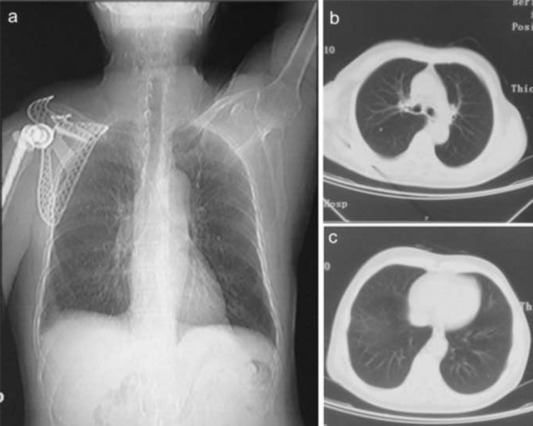

Laboratory tests showed that the serum concentration of CEA reached 17.64 ng/ml. Imaging: X-ray (Fig. 1 a) showed the destruction of the right scapula, and a shadow of soft tissue mass in right scapular region; CT (Fig. 1 b) showed right scapula destructed, surrounded by irregular low-density mass shadow. MRI (Fig. 1 c, d) showed a shadow of soft tissue mass inside of right shoulder, two rounded nodule below the right clavicle, considering as a malignant tumor of the right scapula, right subclavian lymph node metastasis. Emission computed tomography (ECT) showed high metabolism activity in the right scapula, right shoulder and right clavicle bone (Fig. 2 ). Preoperative needle biopsy report: clear cell sarcoma (Fig. 3 ); immunohistochemical staining: PCK (−), LCA (−), Melanoma (−), Syn (+), desmin (−), S-100 (+), CD68 (±), vimentin (+).

Fig. 2.

ECT showed high metabolism activity in the right scapula, right shoulder and right clavicle bone.